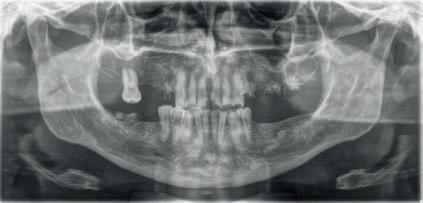

A PROPÓSITO DE UN CASO Paciente hombre de 52 años de edad que acude a la consulta demandando tratamiento implantológico para varias ausencias dentales y la restauración de los dientes remanentes (Figuras 1 y 2). El caso fue estudiado mediante modelos diagnósticos, exploración clínica y radiográfica.

Figura 2. Imagen radiográfica de diagnóstico inicial mostrando la ausencia de piezas dentales en los sectores posteriores, la presencia de diferentes grados de desgastes dentales y raíces dentales remanentes. También muestra la presencia de varias lesiones periapicales.